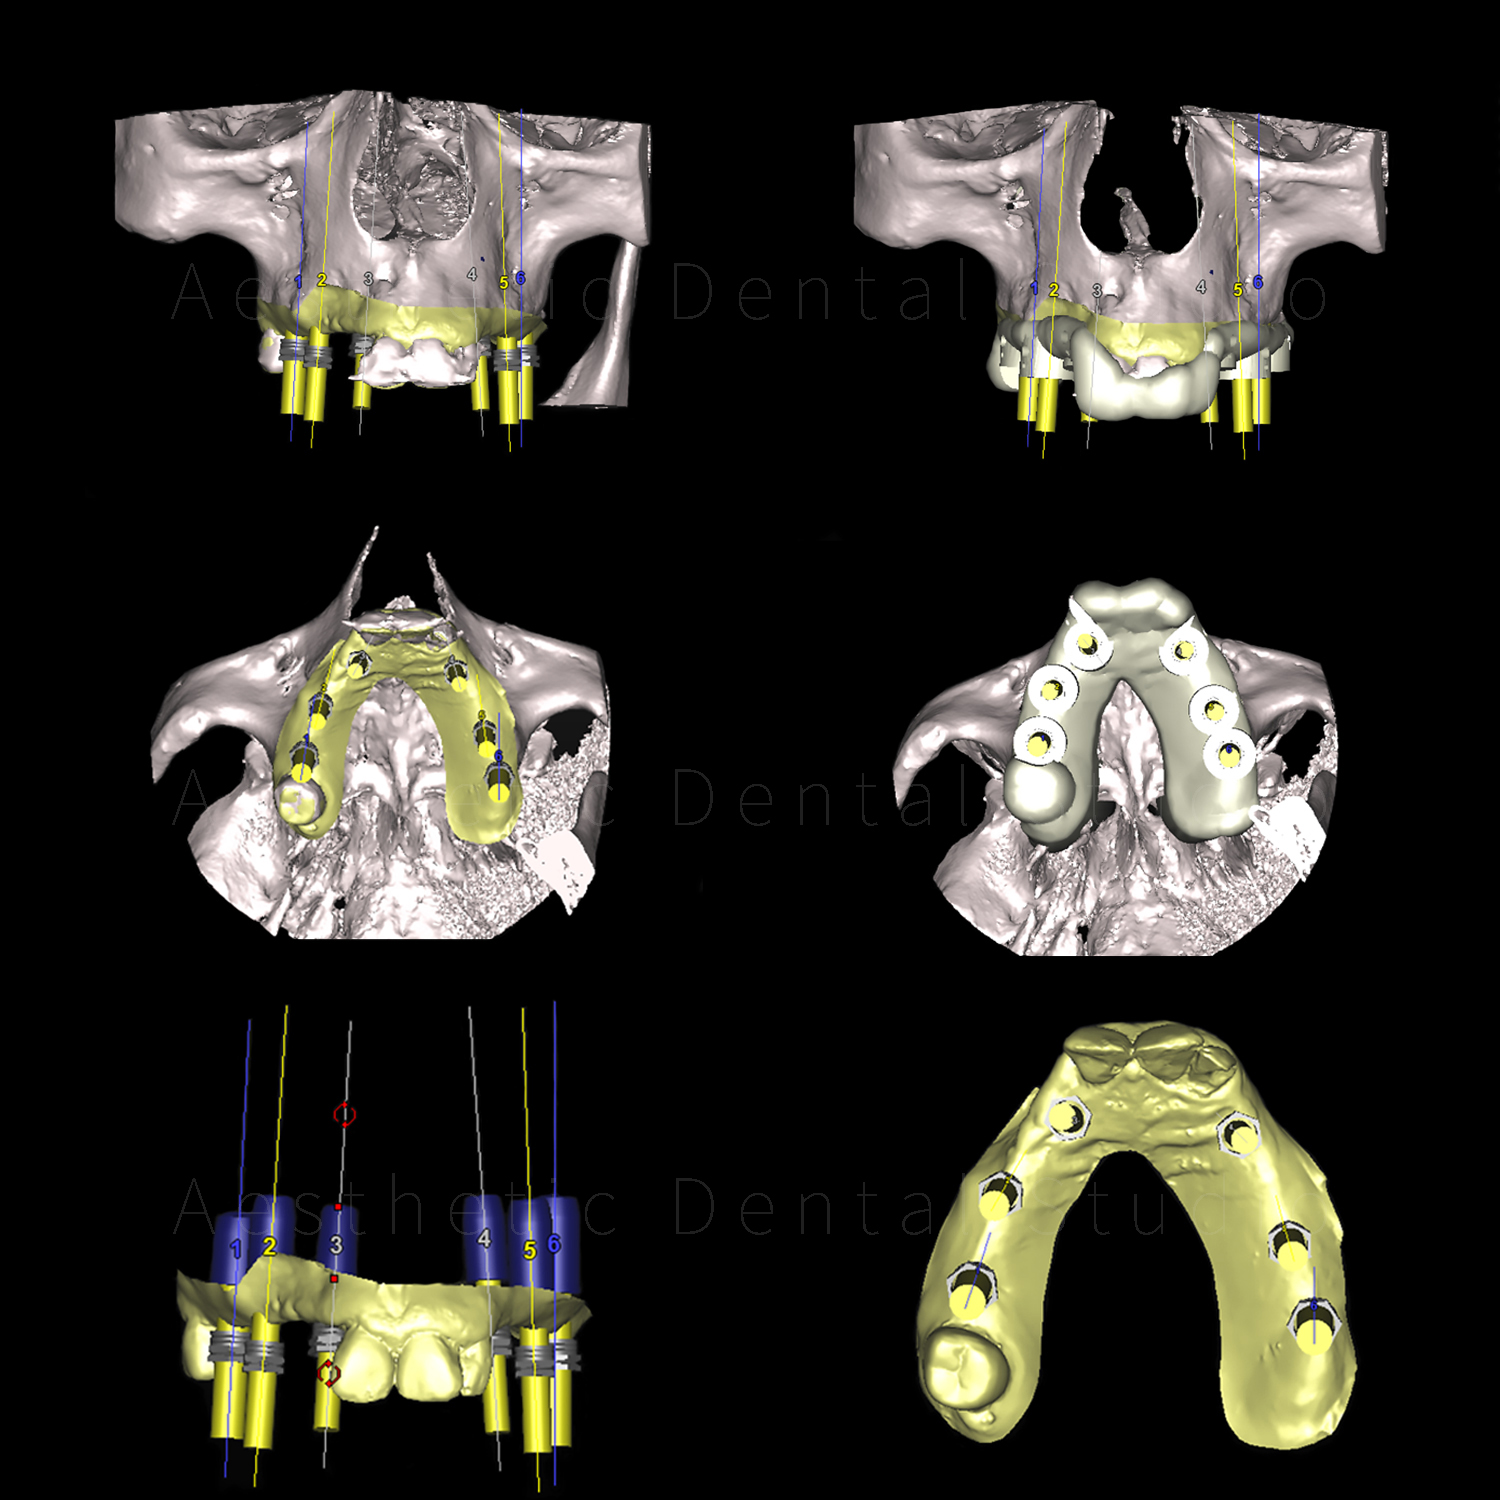

Με εξειδικευμένο οδοντιατρικό λογισμικό έγινε ψηφιακός σχεδιασμός και εικονική τοποθέτηση των εμφυτευμάτων, ώστε να εξασφαλιστεί απόλυτη ακρίβεια και ασφάλεια.

Ο σχεδιασμός στάλθηκε σε εξειδικευμένο κέντρο στη Γερμανία, όπου δημιουργήθηκε τρισδιάστατος χειρουργικός οδηγός, προσαρμοσμένος στο στόμα της ασθενούς.

Αυτός ο οδηγός χρησιμοποιήθηκε στο χειρουργείο για την τοποθέτηση συνολικά 11 εμφυτευμάτων με ακρίβεια χιλιοστού:

• 6 στην άνω γνάθο

• 3 στην κάτω δεξιά περιοχή

• 2 στην κάτω αριστερή περιοχή